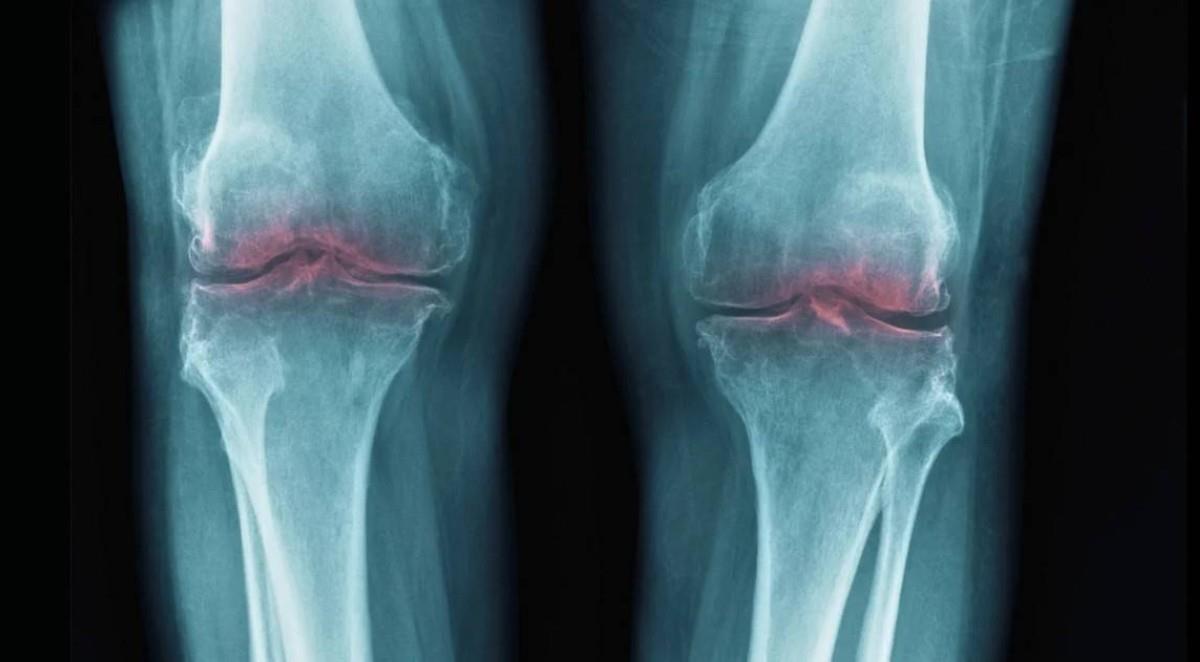

ستانفورد: أمل جديد لعلاج خشونة المفاصل عبر تجديد الغضاريف بدل تسكين الألم

توصل فريق من الباحثين في مركز ستانفورد ميديسين (Stanford Medicine) بولاية كاليفورنيا إلى نتائج بحثية واعدة قد تُحدث تحولاً في طرق التعامل مع التهاب المفاصل التنكسي (الفصال العظمي)، بعد نجاح تجاربهم في تحفيز تجدد غضاريف المفاصل المتآكلة لدى فئران مسنّة، ما يفتح الباب أمام علاجات لا تكتفي بتخفيف الألم، بل تستهدف إعادة ترميم المفصل نفسه.

وأظهرت التجارب التي أُجريت على الفئران نتائج مشجعة، حيث تحسنت سماكة غضروف الركبة المتآكل، وارتفعت القدرة على الحركة والمشي، مع تراجع مؤشرات الألم، إضافة إلى الحد من تطور الخشونة في حالات إصابات شبيهة بتمزق الرباط الصليبي.

ويكتسي هذا التطور أهمية خاصة، بالنظر إلى أن العلاجات الحالية لخشونة المفاصل تركز في الغالب على تخفيف الأعراض فقط، عبر المسكنات والعلاج الفيزيائي والحقن الموضعية، بينما يُعد التدخل الجراحي واستبدال المفصل الخيار الأخير في الحالات المتقدمة، ما يجعل هذه النتائج خطوة محتملة نحو مقاربة علاجية أكثر جذرية في المستقبل.